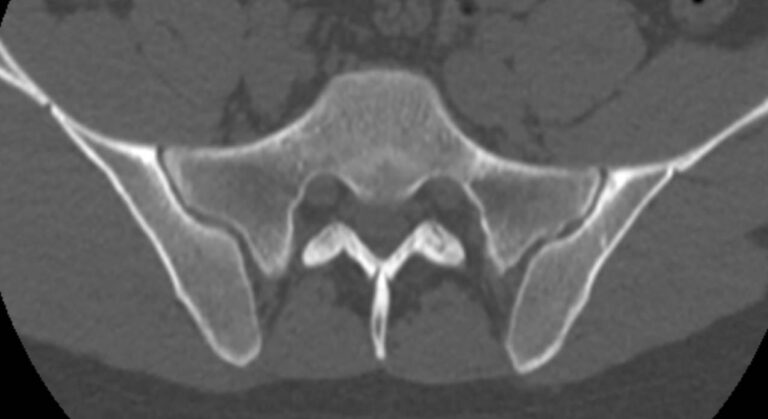

Мультиспиральная компьютерная томография – это современный наиболее достоверный метод диагностики различной патологии крестцово-копчикового сочленения, основанный на послойном сканировании органов и тканей с использованием рентгеновских лучей. Благодаря получаемым тонким срезам с шагом от 0,5 мм и последующей обработке данных компьютерными программами удается получить изображения костных структур, связочного аппарата, межпозвоночных дисков и окружающих тканей. В дальнейшем данные могут быть преобразованы в 3D-изображения исследуемой анатомической области. Это позволяет выявлять различные заболевания позвоночника на ранних стадиях и назначать своевременное лечение.

КТ крестцово-копчиковой области может выявить наличие следующих патологий:

- вывихи в крестцово-копчиковом сочленении;

- остеохондроз;

- септическую, туберкулезную или метастатическую деструкцию крестца;

- остеопороз (визуальная оценка);

- Смещение или перелом позвонков, а также оценить локализацию отломков позвонков;

- гематомы в области поврежденной области;

- воспалительные процессы;

- новообразования и метастазы;

- последствия травм и операций;

- дегенеративно-дистрофические изменения.